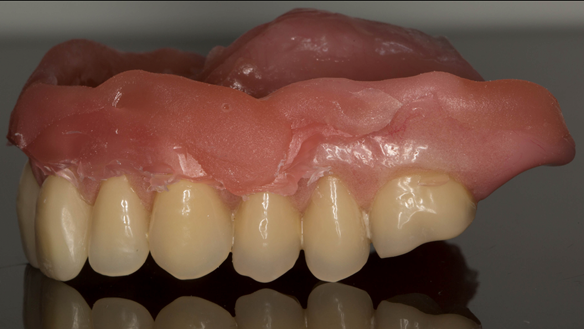

This newsletter describes in step by step detail Anne's transition from an immediate complete upper denture to a definitive complete upper denture.

The clinical situation and treatment process is shown in detail below with photographs. In addition, threre is a link to the a 45 minute webinar I gave explaing this case. I provided the clinical work and Rowan Garstang provided the technical work.